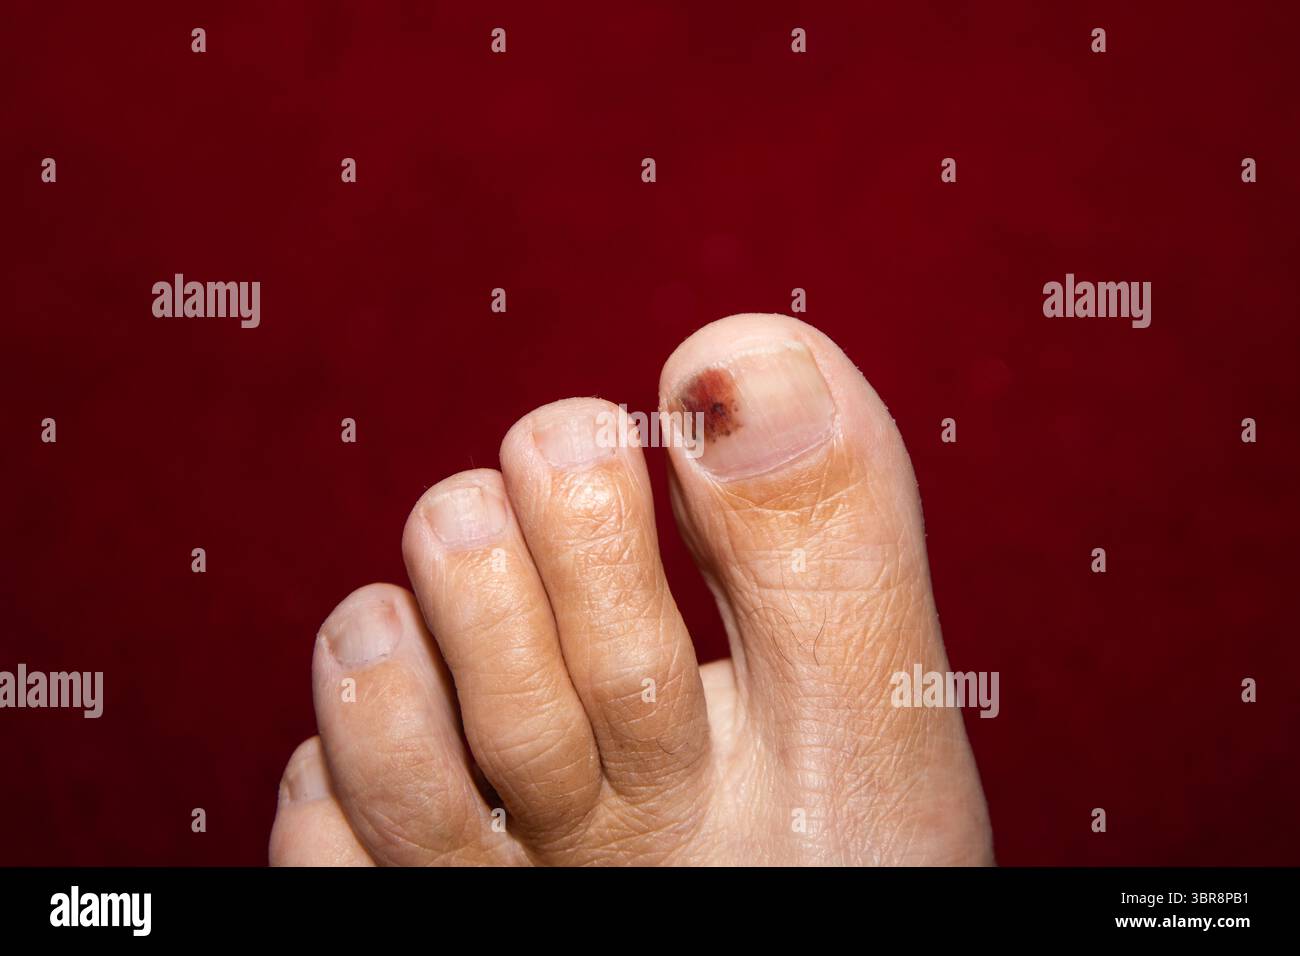

RF3BR8PB1–Nahaufnahme eines blauen großen Zehens mit sichtbaren subungualen Blutergüssen unter dem Zehennagel, die Verfärbungen und Traumata zeigen, die häufig durch Aufprall oder Druck verursacht werden

RF3BR8PPJ–Nahaufnahme eines blauen großen Zehens mit sichtbaren subungualen Blutergüssen unter dem Zehennagel, die Verfärbungen und Traumata zeigen, die häufig durch Aufprall oder Druck verursacht werden